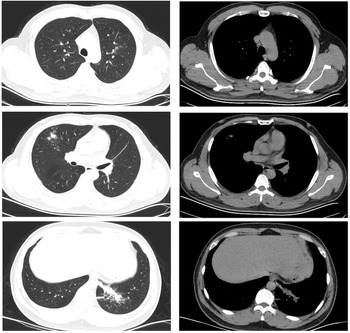

Case 4 and case 5

Both patients experienced fever with slightly elevated body temperatures. They had no complaints of respiratory symptoms. Since the time of disease onset coincided with the COVID-19 outbreak, the patients visited our fever clinic in order to be screened for COVID-19 infection. Upon examination, both patients were found to have pneumonia (Figs 4 and 5). Pathogen testing on pharyngeal swabs obtained from the patients was positive for adenovirus DNA and negative for the other pathogens tested. Case 4 patient was treated by oral administration of arbidol and intravenous infusion of moxifloxacin for 4 days. Case 5 patient did not receive any special treatment, and subsequently his condition stabilised.

Fig. 4. Chest CT of case 4.

Fig. 5. Chest CT of case 5.